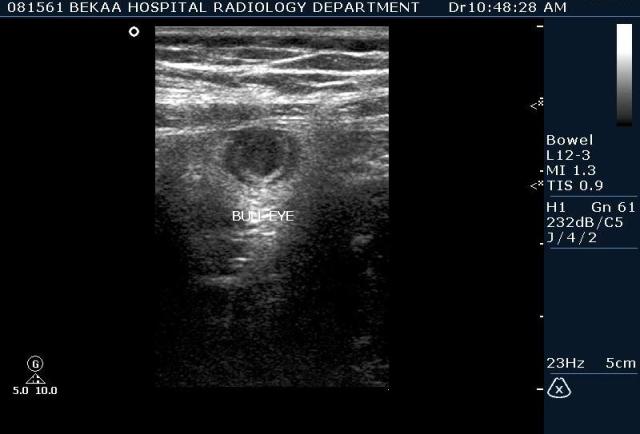

Диагностика острого аппендицита по УЗИ: очень актуальная тема; УЗ аппараты практически есть во всех клиниках; метод доступный и не сложный; главное владеть правильной техникой. Не буду загружать лишней теорией и разными ссылками; поделюсь практическим опытом. У меня линейный датчик 3-12 мегагерц с плавающей частотой; аппарат Филипс HD 11, всегда включаю соно-КТ (9800 цифровых каналов) и гармонику когда смотрю кишечник. Нормальный аппендикс видеть можно; но вопрос зачем??? Как правило, если при наличии достаточного опыта аппендикс не виден; значит скорей всего аппендицита нет. Когда "идешь" на аппендицит то главное по началу набраться терпения и......хорошая компрессия! По началу надо минут 10-15; потом когда появится достаточный опыт; за 2-5 минут можно справится и получить отличную визуализацию. Мочевой пузырь лучше опорожнить; часто он приподнимают тонкий кишечник и может закрыть "окно" через которое будет видно апендикс. Сначала находим слепую кишку потом находим илео-цекальное соединение;

после начинаем производить хорошую компрессию датчиком попрося пациента сообщить в какой точке боль наиболее выражена; медленными движениями датчика сканируем область наибольших болевых ощущений и как правило находим утолщенный отросток. Лучше начинать с поперечной визуализации и идти к верхушке аппендикса что бы убедится что это аппендикс и он заканчивается, а не тонкая кишка (которая если и закончится то только переходя в слепую); потом надо аккуратно развернуть продольно датчик и посмотреть от верхушки аппендикса к слепой. Норма диаметра: 3-4 мм; 5-6 мм под вопросом (клиника решает; но я в катаральный аппендицит не верю); 7-8 мм и больше, не компремируемый (фиксированный отросток)-острый аппендицит! Помимо наличие утолщенного аппендикса; признака "бычьего глаза" (bull-eye sign) при поперечном сканировании; надо обращать внимание на присуствие аппендоколитов в просвете; деструкцию стенки и свободной жидкости в зоне интереса.